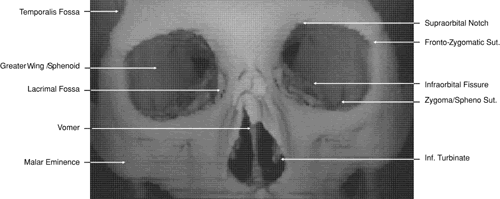

The globe is shown in Figure 12. The orbit and periorbital structures are shown in Figures 13 through 16, and the optic canal is shown in Figures 17 through 26. The cavernous sinus and optic chiasm are shown in Figures 27 and 28, and the posterior visual pathway and cranial nerves are shown in Figures 29 through 33.

Fig. 13. Three-dimensional reconstruction of orbit and infraorbital structures (Water's view).

Fig. 14. Three-dimensional reconstruction of orbit (anterior view).

Fig. 15. Three-dimensional reconstruction of orbit and cranial cavity (superior view).

Fig. 16. Three-dimensional bone reconstruction of cranial cavity structures (view from posterior cranial fossa).